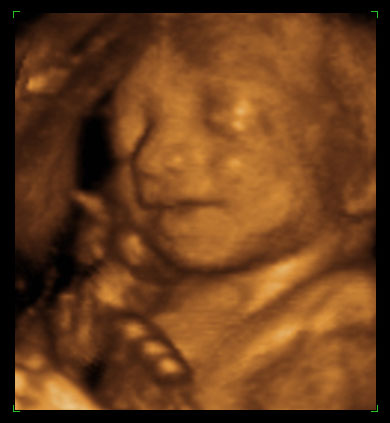

The baby above is of the age that most partial birth abortions were done.

Now, is the term “partial-birth abortion”barbaric and grotesque, or is the procedure itself barbaric and grotesque?